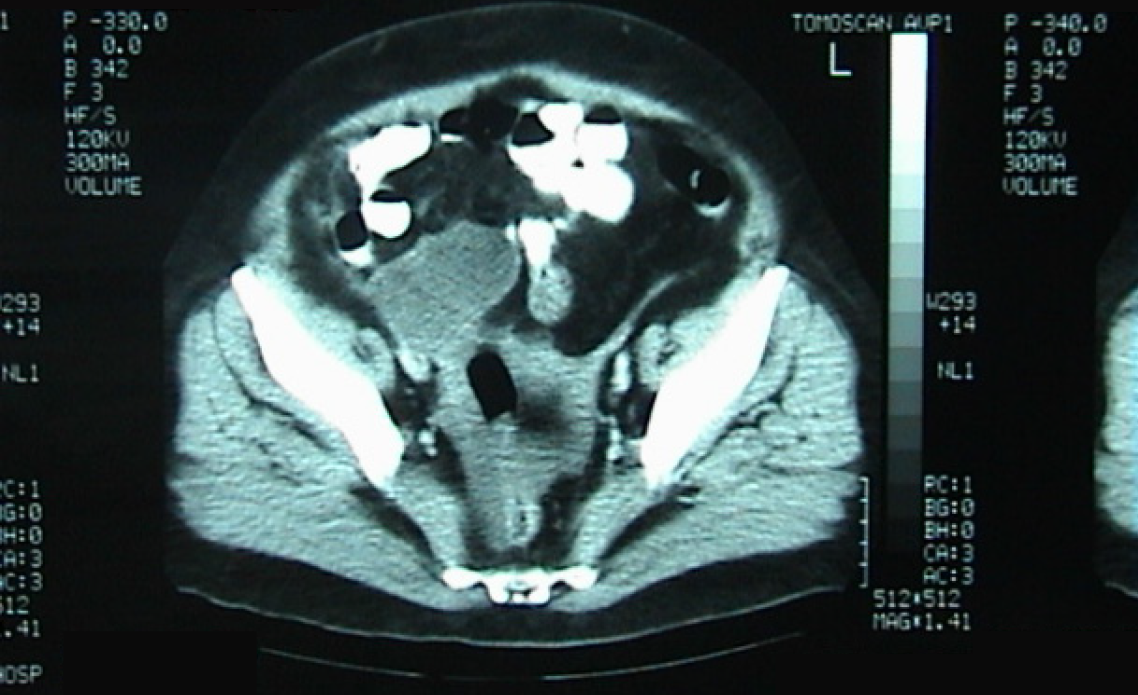

Figure 3 Computed tomography scan with intravenous contrast showing a well-circumscribed, low fluid attenuation tubular-shaped structure, seen in continuation with the base of the cecum, grossly measuring 64 mm × 29 mm × 28 mm, corresponding to the appendix (orange arrow).